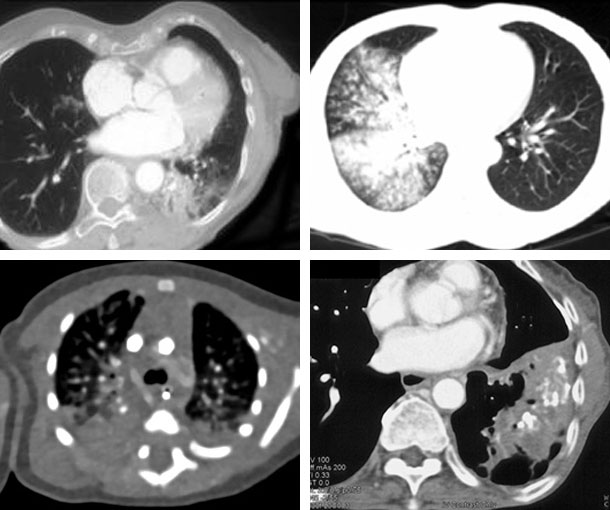

Chest CT Appearances

Aspiration Pneumonia CT Findings

- Alveolar infiltrates

- Low attenuation intrabronchial material

- Centrilobular nodules

- Ground glass attenuation

- Atelectasis

- Bronchiolectasis

- More common in right lung and lower lobes

- May find foreign body, which can be soft tissue or fat